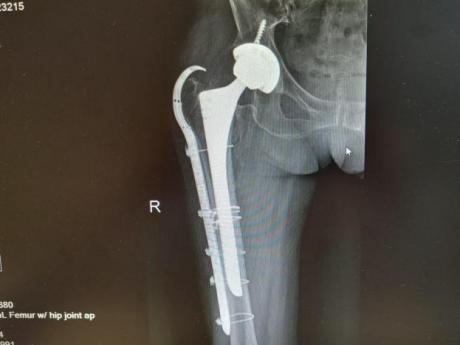

多年来,贵州航天医院各科室紧跟医学前沿,不断强技术、补短板,大力开展新技术、新项目,完成了许多高精尖、高难度、本地区“首例”的技术,填补了医院医疗技术空白,满足了群众日益增长的医疗需求。 贵州航天医院骨科率先在遵义地区开展骨搬移技术,截至目前,已治愈慢性骨髓炎、感染性骨不连、骨缺损、脉管炎、糖尿病足患者200余例,糖尿病足治疗保肢率达到98%。 本期,我们将为大家带来骨科特色技术——骨搬移技术(Ilizarov)。 案例分享 一名59岁的患者,身患糖尿病12年,在来我院3个月前出现了右脚溃烂的症状,来院就诊时,患者的右脚十分红肿,右脚脚趾坏死,伤口处不断流出黑红色脓液,情况十分严重。在接诊到患者时,骨科专家团队高度重视,立刻为患者完善了CT血管造影(CTA)等相关检查,诊断为:2型糖尿病,糖尿病周围血管病变,右糖尿病足。 术 前 考虑到患者情况比较严重,为最大限度保证患者肢体完整,科室专家团队进行了严格的讨论评估,为患者制定了骨搬移技术治疗方案,在征得患者及其家属的同意后,成功通过搬移骨块为患者进行治疗,促进患者病变肢体血管再生。 胫骨横向骨搬移外架固定 清除感染病灶 术后调节外架,通过搬移骨块 促进患肢血管再生 患者在术后三周前来换药,观察到感染得到进一步控制;术后六周复查,患者病变处已愈合,进行CT血管造影(CTA)后可明显观察到足部血管再生。 术后3周 术后6周愈合 CT血管造影见足部血管再生 糖尿病患者全身与局部的问题互为影响,形成恶性循环,糖尿病足溃疡创面迁延不愈,常见干性坏疽、湿性坏疽、趾坏死、深且大的溃疡以及骨髓炎等症状,还可导致脓毒血症,以往为保全生命,患者被迫选择一次或多次截肢。骨搬移技术的发展进步,能在血糖有效控制、局部有效清创下,有效促进患肢微血管再生,改善患肢血供,达到糖尿病足更快治疗康复的目的,并能根据病变情况最大限度的保障患者肢体完整。 什么是骨搬移技术 骨搬移技术是通过使用专用的骨外固定器固定骨段,每天缓慢牵拉,在牵拉搬移过程中,骨段尾部形成新骨及新的软组织,从而修复骨骼缺损及软组织缺损。是治疗大段骨缺损、骨不连、骨感染、肢体畸形的金标准方法,也用于治疗脉管炎、糖尿病足等肢体缺血性疾病。 骨感染缺损 切除感染段 搬移骨段 新骨形成 骨感染根治愈合 骨搬移技术原理 生物组织在持续、稳定、缓慢牵拉下,能刺激细胞分裂、组织再生,骨外固定技术运用该原理,通过持续缓慢调节外固定器形成牵拉张力,促进牵引成骨与相邻组织再生,如神经、血管、肌肉、皮肤等再生,达到治疗大段骨缺损、肢体缺血如糖尿病足等疾病的目的。 骨搬移技术优势 (一)除治疗骨缺损、骨不连外,有更广的适用范围,利用组织再生、血管再生等特性,能大量运用于肢体畸形的矫形、糖尿病足等的治疗。 (二)治疗效果确切,重建肢体外型和功能,极大降低截肢率和残疾率。 (三)明显提高了患者生活质量,极大减轻其家庭及社会负担。 肢体畸形的矫形 慢性骨髓炎 骨段切除 术后1年 濒临截肢的脉管炎术后6周 难愈创面术后3周 贵州航天医院骨科 专家团队 赵学平 骨科主任 主任医师 临床擅长:从事骨科临床工作30余年,对骨科常见疾病的诊治具有丰富的临床经验。 世界中医药联合会脊柱康复专业委员会常务理事,中华中医药学会整脊分会常务委员,中国中西医结合学会骨伤科分会肢体矫形功能重建与康复专家委员会常务委员,中国研究性医院学会骨科创新与转换专业委员会关节外科学组保髋工作委员会常委,中国康复技术转化及发展促进会骨外科与康复技术转化专业委员会常务委员,泛珠三角区域运动医学联盟(PPRD-SMA)理事会常务理事,中国研究型医院学会运动医学专业委员会委员,贵州省中医药学会整脊分会副主任委员,贵州省中西医结合学会银质针专业委员会副主任委员,贵州省康复医学会骨与关节专业委员会常务委员,贵州省人民医院骨科专科联盟常务理事,贵州省康复医学会骨内科专业委员会常务委员,中华医学会贵州省骨科学会委员,贵州省康复医学会脊柱脊髓专业委员会常务委员,贵州省运动医学分会委员,贵州省康复医学会骨与软组织肿瘤专业委员会委员,遵义市医学会创伤分会副主任委员,贵州省康复医学会骨内科专业委员会遵义地区分会常务委员,遵义市医疗事故鉴定、伤残鉴定、工伤鉴定、司法鉴定专家。 长期从事骨科临床研究及教学工作,在国家级、省部级杂志发表论文20余篇,SCI论文2篇,参与主编骨科专著2部,主持省部级科研项目2项,参与指导省部级、市级科研项目6项。 陈明勇 骨科副主任 副主任医师 临床擅长:从事创伤骨科工作约20年,对骨缺损、骨不连、骨肿瘤、肢体畸形等的肢体矫形重建及功能重建,慢性化脓性骨髓炎的根治治疗、糖尿病足的保肢治疗、快速康复理念(ERAS)下的老年骨折的诊治,四肢复杂骨折的诊治,四肢骨折等微创手术治疗具有丰富的临床经验。 2004年毕业于遵义医学院临床专业,曾在中国人民解放军总医院、广西医科大学第一附属医院、上海第六人民医院骨科进修。中国中西医结合学会骨伤科专业委员会横向骨搬移治疗糖尿病足及微血管网再生学组首届委员,遵义市医学会创伤分会常务委员。 瞿 辉 骨科 副主任医师 临床擅长:对骨科的常见病、关节外科、脊柱外科及运动医学疾病的诊治具有丰富的临床经验,熟练掌握骨科手术操作技术。 毕业于遵义医学院临床医学系,2005年前往广州中山大学第一附院骨显微医学部进修学习,2011年前往成都华西医院进修学习,并多次在省内外学习骨科相关知识,是中华医学会骨科分会会员。 赵兴东 骨科 主任医师 临床擅长:擅长骨科的常见病及各种创伤、四肢骨折创伤修复、骨感染、手足疾病的诊治和手足体表畸形的矫形整复,熟练掌握骨科四肢骨病及创伤的手术操作技术,尤其在四肢关节复杂性损伤、手足外伤、组织缺损创面、难治创面的皮瓣修复方面及平足、高弓足矫形方面及四肢慢性疼痛诊治、康复方面具有丰富的临床经验。 硕士研究生,毕业于遵义医学院临床外科系,2015年前往山东省立医院手足外科进修学习;遵义市医学分会创伤分会第一、二届委员,遵义市手外科医学会第二委届员会常务委员;在省级及省级以上期刊发表文章9篇,参编著作2部,参与主持并完成市级课题1项,参与市级课题2项、省级课题1项。 张俊凯 骨科 副主任医师 临床擅长:从事骨科临床工作28年,对创伤骨折、骨感染、骨缺损、骨不连等外科诊治,四肢骨折的微创手术治疗,四肢复杂骨折(如关节内粉碎性骨折、多发骨折等)的损伤控制及手术治疗等具有丰富的临床经验。 1995年毕业于遵义医学院临床专业,2009年前往复旦大学附属医院骨科进修1年。 卢懿明 骨科 副主任医师 临床擅长:从事骨科工作18年,对创伤骨折、四肢骨折的微创手术治疗、四肢复杂骨折(如关节内粉碎性骨折、多发骨折等)的损伤控制及手术治疗,尤其是髋部骨折的PFNA等微创技术,踝关节骨折、膝关节周围骨折的Mipo微创技术等具有丰富的临床经验,开展了4项新技术,发明6项新型专利技术。 2005年毕业于遵义医学院临床专业,2017年,前往南方医科大学第三附属医院骨科进修半年,回院后运用Mipo技术对骨干骨折及干骺端骨折的治疗技术,同时积极开展骨盆骨折、髋臼骨折腹直肌外侧切口的应用;发表了多篇专业论文,经常参与省内外学术交流会授课,获得医院荣誉称号多个。 邬夏荣 骨科 副主任医师 临床擅长:从事骨科工作16年,对四肢复杂骨折、骨肿瘤的诊治,尤其是足踝创伤、慢性踝关节损伤、平足症等诊疗具有丰富的临床经验。 2006年毕业于遵义医科大学临床医学专业,曾在陆军军医大学西南医院进修学习,发表多篇骨科学术论文。 余德怀 骨科 副主任医师 临床擅长:从事骨科工作10余年,对运动医学、骨关节、脊柱外科常见病、多发病的诊治具有丰富的临床经验。 硕士研究生,2011年毕业于遵义医学院临床医学专业,曾前往遵义医科大学附属医院运动医学专业进修学习;是贵州省医学会运动医学分会青年委员,西部关节镜联盟委员;发表多篇骨科学术论文。 冯 乾 骨科 副主任医师 临床擅长:从事骨科工作近20年,熟练掌握骨科多发病及常见病的诊治,尤其对脊柱退变性疾病的诊断及治疗具有丰富的临床经验,主要研究脊柱微创相关治疗方式,能熟练开展椎间孔镜及VBE。 曾前往北京大学第三医院进修学习疼痛及椎间孔镜、首都医科大学友谊医院专业进修脊柱内镜;是贵州省康复医学会第三届脊柱脊髓专业委员会委员;发明专利3项、发表脊柱外科专业论文多篇。 张艳金 骨科 副主任医师 临床擅长:从事骨外科工作16年,对复合伤、多发伤的救治、四肢骨干骨折、关节周围骨折、骨肿瘤、骨髓炎等诊治具有丰富的临床经验。 中共党员,硕士研究生,2006年本科毕业于山西医科大学第二临床医学院,2011年研究生毕业于北京军区总医院;在“老年COPD患者合并髋部骨折的诊治”国际合作课题组研究两年,在老年髋部骨折的诊治方面具有丰富的经验,并发表论文6篇;承担遵义市级课题1项;承担遵义医科大学的临床教学工作,获得遵义医科大学优秀带教老师荣誉。编撰有《骨科疾病诊疗精粹》一书,开展2项新技术,编撰地方规范《务川自治县创伤骨科常见疾病诊疗规范》一书。 赵小锋 骨科 副主任医师 临床擅长:从事骨科临床工作11年,对骨科常见病、多发病诊疗有较为丰富的临床经验,擅长脊柱相关疾病诊断及治疗,尤其是颈、腰、腿疼痛疾病诊断及治疗,擅长胸腰椎骨折微创经皮穿刺内固定术、经皮穿刺椎体成形术、经皮穿刺脊柱内镜下腰椎间盘摘除术、单纯开创腰椎间盘摘除术、腰椎滑脱复位椎间植骨椎融合内固定术、腰椎管狭窄减压融合内固定术及人工髋、膝关节置换术等。 2012年毕业于遵义医学院外科学专业硕士研究生,2019年参加“遵义市115医学人才精英计划”于上海交通大学第一附属医院培训学习,2023年于北京大学第三人民医院脊柱外科进修学习,曾获得遵义市优秀医师荣誉称号。 遵义市手外科第一届委员,遵义市医学会创伤分会第一届委员,遵义市医学会创伤分会第二届委员,贵州省康复医学会第三届脊柱脊髓专业会委员,遵义市医学会烧伤与整形外科学分会委员,发表论文5篇,其中国家级核心期刊1篇,SCI论文1篇,主持市级课题1项并结题,参与市级课题2项。 贵州航天医院骨科简介 基本情况 贵州航天医院(原3417医院)骨科组建于1968年,前身是以创伤和断肢(断指)再植闻名于世的上海市第六人民医院骨科,中国断肢(断指)再植的奠基者、中科院院士陈仲伟等著名专家、学者多次莅临科室指导医疗、教,是贵州省最早拥有专业骨科技术科室之一,在70年代开展了贵州省首例断肢(断指)再植手术。组建50余年来,诊治患者已逾百万,挽救了无数的伤病员,成为了保障遵义地区人民群众健康的重要支撑。 经过几代人的不懈努力,今天的骨科,已由创伤骨科发展至骨病、骨肿瘤、骨结核等领域,现有脊柱外科、关节外科、四肢创伤、手足外科四个亚专科,成为了集医疗、教学、科研于一体的综合学科,是贵州省临床重点专科、遵义市临床重点专科、遵义市骨科临床医学中心、遵义市基层骨科专科联盟理事长单位。 科室目前开放床位110张,共有医护人员50余人,副高级以上专家18人,硕士研究生15人。拥有一流骨科医疗设备多台,每年不定期选派优秀技术骨干到全国各大知名医学院校进修、学习、参观、交流,并邀请国内、国外知名专家教授来院进行交流、指导,通过不断引进国内外先进的诊疗技术,科室医疗技术水平稳步提升,为广大人民群众提供了优质的医疗服务。 专科特色 骨一科 (一)骨缺损、骨不连的肢体与功能重建 胫骨横向骨搬移技术治疗糖尿病足: (二)慢性骨髓炎的根治治疗 (三)肢体缺血性疾病如糖尿病足、脉管炎的保肢治疗 (四)皮瓣修复 (五)复杂创伤的治疗 (六)老年髋部骨折及小儿骨折快速手术 老年髋部骨折: 骨二科 (一)胸腰椎骨折微创经皮椎弓根螺钉固定术 (二)老年性骨质疏松性患者腰椎滑脱脊柱内固定术(骨水泥螺钉) (三)V形双通道脊柱内镜技术(VBE)腰椎融合术治疗腰椎退行性疾病 (四)老年性骨质疏松性骨折(PVP/PKP)术 (五)人工髋关节置换术 (六)双侧股骨头坏死人工全髋关节置换 (七)右侧全髋置换术后假体周围骨折翻修 (八)人工膝关节置换术 (九)人工膝关节假体松动翻修 (十)关节镜技术 传统手术切口 关节镜技术切口 诊疗范围 骨一科 1.四肢创伤、矫形。 2.手、足踝外科。 骨二科